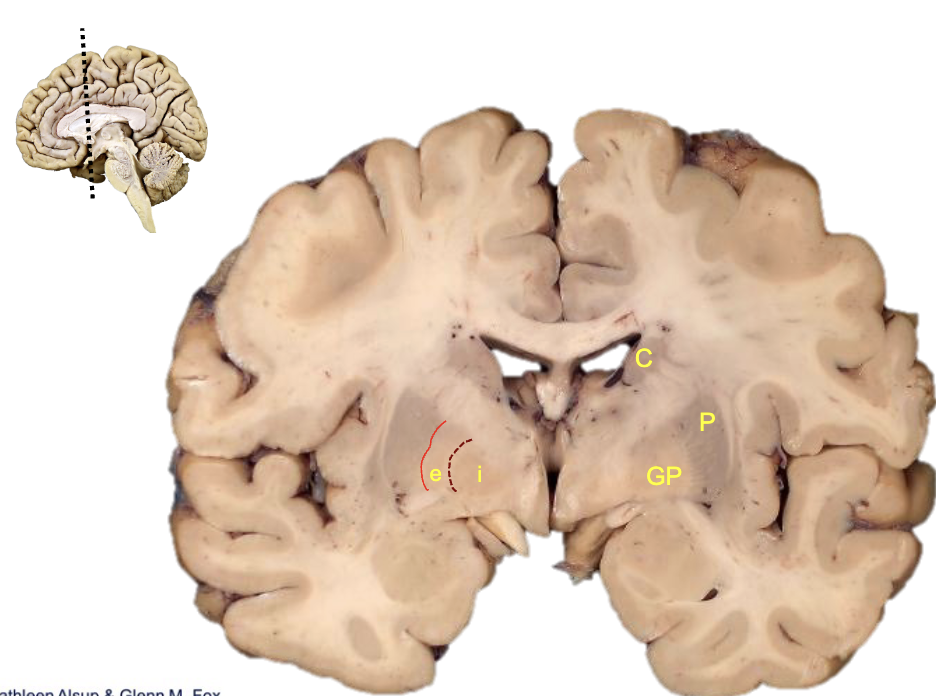

<p><strong>what is c?</strong></p>

what is c?

caudate

<p><strong>what is p?</strong></p>

what is p?

putamen

<p><strong>what is gp?</strong></p>

what is gp?

globus pallidus

<p><strong>what is i?</strong></p>

what is i?

internal segment

<p><strong>what is e?</strong></p>

what is e?

external segment